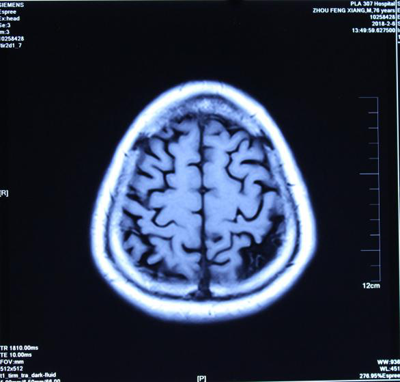

报告单1(治疗前) 报告单2(治疗后) 报告单1是孙先生治疗前, 2014年9月23日进行核磁共振(MRI)检查报告中检查所见:“幕下小脑、脑干亦萎缩明显”。报告单2是孙先生治疗后: 2014年11月29日用纯中药治疗2个月后,进行核磁共振(MRI)检查报告中检查所见:“幕下小脑未见异常信号”。临床症状明显消失。 典型病例二(影像比较):脑细胞再生长使脑组织增长 患者:周先生 男 76岁 退休干部,治疗前面无表情、意识不清,不能自己活动等。做核磁共振检查进行治疗前后比较如下:

图1-1 (治疗前) 图1-2(治疗前)

图1-3 (治疗后) 图1-4(治疗后) 上图是严重脑萎缩用中药治疗半年核磁共振影像的前后对比:周先生 男 76岁 面无表情,意识不清,记忆严重减退二年余,肢体活动困难,病情渐渐加重,对自己名字不知道,自己吃的什么饭不清楚,不能自己行走等病情,临床诊断为:阿尔茨海默病(老年痴呆症),脑中风后遗症。2018-年02月06日磁共振影像显示:脑萎缩(图1-1、图1-2下端黑洞脑组织严重缺损)。经中药治疗半年,患者面部病情正常,意识恢复正常,对自己的名字及他人都清楚,吃过的食物过后也记得,能够与他人正常交流,能够自己行走活动。2018年8月3日核磁共振影像(图1-3、图1-4)显示:脑萎缩与2018年2月6日(图1-1、图1-2)比较脑萎缩明显恢复(脑组织严重黑洞缺损消失)。影像证明了:经治疗使的脑细胞再增长,使脑组织增多,使脑组织逆生长。 我们编著了《大脑复原理论 大脑细微结构修复术》(成了脑科研究的参考资料)以及近期编著了《大脑复原理论 大脑医疗技术探秘》,介绍了脑细胞再生长的原理和临床治疗成功的验证,是我们中国人在国际上首先提出了脑细胞再生长和成功做到了脑细胞再生长!我们对大脑萎缩、小脑萎缩、脑科疑难疾病的有效治疗,是用核磁共振进行治疗前后的对比。 2016年6月在中国海南博鳌召开的“2016世界医疗旅游和世界健康学术大会”和2016年7月在曼谷召开的“世界传统医学大会”上,贾学铭教授发表并介绍用纯中药使脑细胞再生长治疗脑萎缩、阿尔茨海默(老年痴呆症)能够治愈的效果,用核磁共振影像片子进行治疗前后的对比,证明脑组织有了新的增多,做到了使脑细胞再生长的效果,改变了过去医学界不可治愈的理论,受到了美国、德国、澳大利亚、意大利、英国、法国等参会的代表和许多国家专家的认可和赞扬。这个“脑细胞能够再生长”的理论,到目前是贾学铭教授和贾沅潽医学博士首先提出的,也是首先用影像证明能够做到的,为人类健康事业流出一定的贡献。 在党的十八大以来,为强我中华,创新中医、发展中医,创新做到了用中医中药的方法,艰难的创新再创新的实践,做到了脑细胞再生长、脑组织能够再生长,造福了脑科疑难病患者,脑细胞再生长,治疗了大量的脑萎缩病人。对脑科医学理论和脑科疑难病治疗有重要的参考意义。在国际上产生了很好的影响,显示了中国中医药的魁宝,2016年7月在曼谷召开的世界传统医学大会上获得了《世界传统医学突出贡献奖》和《世界传统医学终身成就奖》。对现在及往后的脑科研究和脑科疑难病的治疗有重要的意义,为国际脑科医学的研究和治疗做出了显著的贡献。 贾学铭教授,贾沅潽博士介绍: 贾学铭,字:瀚珺,教授, 主任医师,从事中医工作50年,资深中医专家,中医脑科专家,中国传统医学名医,中国名人俱乐部副主席兼健康委员会主任,中华中医药学会专家委员,英国中医师学会知名专家、中医顾问,中国生命关怀协会心脑血管病防治指导专家,山东潍坊吉缘堂抗衰老中医药研究所法人等职。北京同仁堂中医医院贵宾楼专家,北京同仁堂王府井中医院心脑血管病专家,301医院远程医学中心专家,301健康管家心脑血管病专家,北京八大处中西医结合医院脑科专家。 贾沅潽医学博士,国外留学10年,2012年回国,山东潍坊吉缘堂抗衰老中医药研究所所长等职。通过我们研究治疗的临床案例等研究,2015年编著了《大脑复原理论 大脑细微结构修复术》,2019年编著了《大脑复原理论 大脑医疗技术探秘》,介绍了脑细胞再生长的原理和治疗的成功验证,是我们中国人在国际上首先提出了脑细胞再生长和成功做到了脑细胞再生长!为脑科医学作出了非常有意义的贡献! |